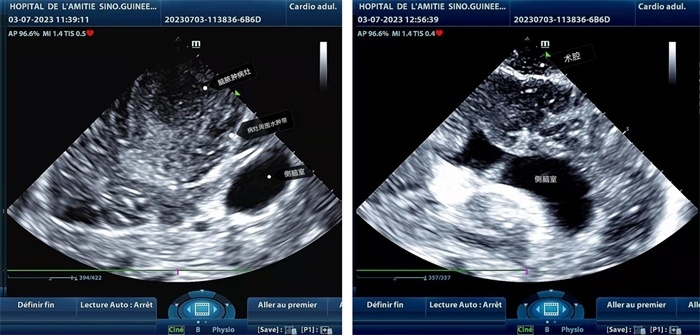

左圖顯示術(shù)中超聲見囊實(shí)性病變,大小約為4x4x3cm,病灶周圍腦組織水腫明顯;右圖為病灶切除后,術(shù)中超聲示術(shù)腔無病變殘留

左圖顯示術(shù)中超聲見囊實(shí)性病變,大小約為4x4x3cm,病灶周圍腦組織水腫明顯;右圖為病灶切除后,術(shù)中超聲示術(shù)腔無病變殘留。中國第二十九批援幾內(nèi)亞醫(yī)療隊(duì)供圖